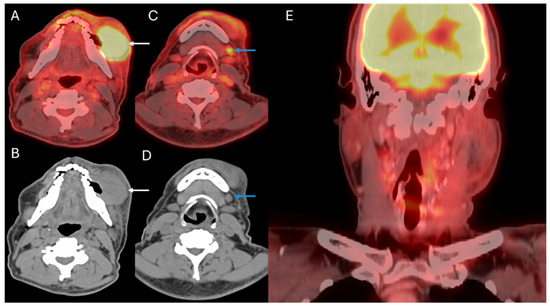

4. Staging of Cervical Nodal Metastases